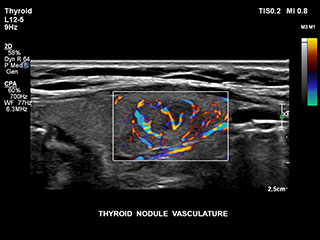

Bisher war die Erfassung von Flussdaten bei kleinen Gefäßstrukturen mit niedriger Flussrate schwierig. Die neue EPIQ Funktion MicroCPA bietet eine schnelle und einfache Darstellung von Mikrozirkulation mit niedriger Geschwindigkeit und ermöglicht eine hohe Diagnosesicherheit bei der Beurteilung der Organperfusion oder von kleinen Gefäßbetten.